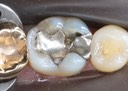

Matt Dodson #30 finish